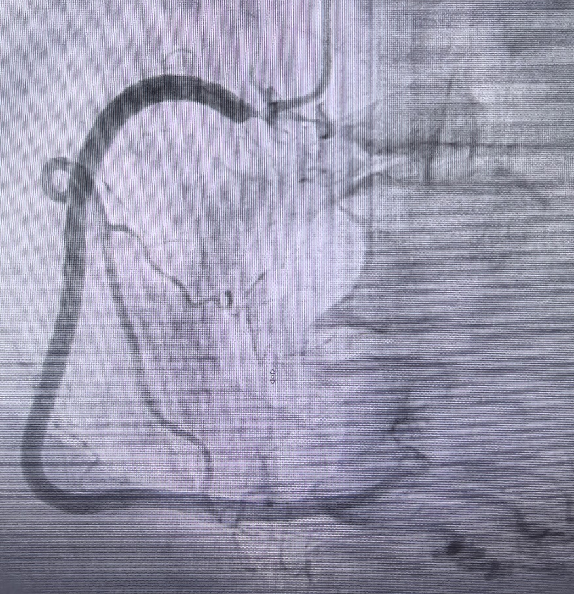

左主干、前降支 轻度狭窄。 右管开口局限偏心 90% 病变。

手术策略

A. 桡动脉入路,6F薄鞘;

B. osRCA B 型病变;

c. 术中患者稳定则先行 IVUS 检查,如导丝通过后患者不稳定,则迅速 POBA 后植入4.0-15mm DES 支架植入。